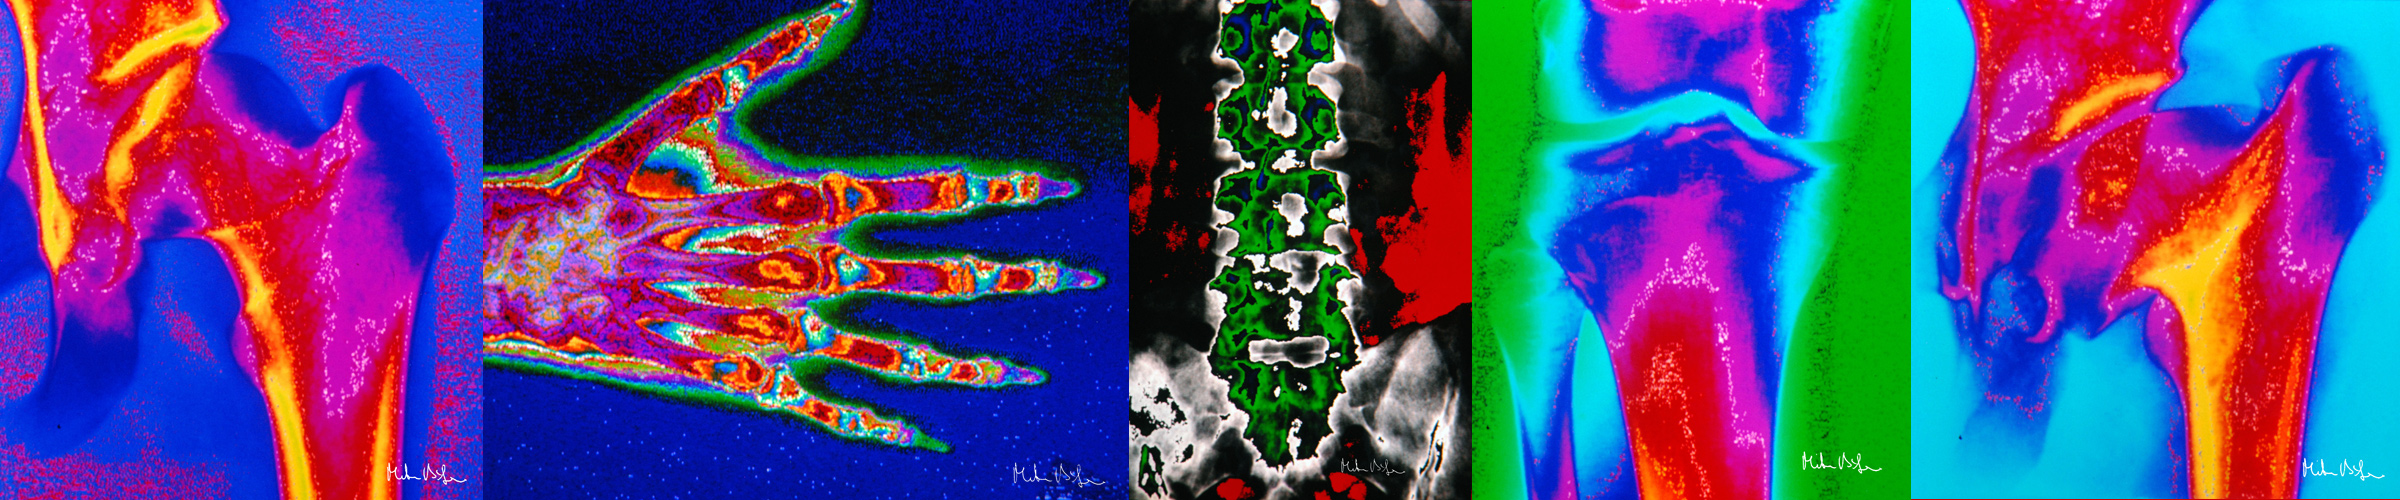

Farbige Röntgenaufnahmen

... gibt es nicht, oder doch? Wie geht das?

Normale Röntgenaufnahmen sind und bleiben auch digital "grau".

Folgende farbige Röntgenbilder entstanden bereits in den Jahren 1989-1990, nachdem die ersten Homecomputer den Commodore 64 ersetzten.

Damals hatte ich im Rahmen eines von der DFG gefördeten Forschungsprojektes normale Röntgenaufnahmen mit einer analogen Videokamera auf einem x86-PC (mit 10MB Festplatte) gespeichert, die Grautöne dann eigens entwickelten Farbtabellen zugeordnet und pseudocolorisiert. Hiervon hatte ich Dias gefertigt, diese jahrelang im Keller vergessen, dann irgendwann entstaubt und digitalisiert.

Bei einem von der Röntgenfirma "Philips" 2009 ausgeschriebenen Wettbewerb "Röntgenkunst" haben zwei dieser farbigen Röntgenaufnahmen sogar den 2. bzw. 4. Preis erhalten.